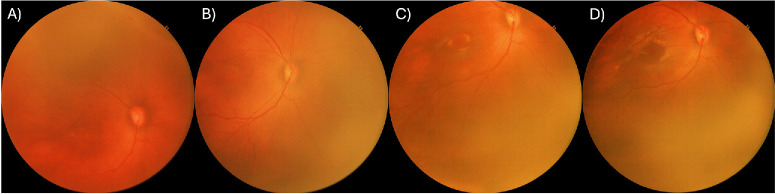

Purpose: Accurate identification of retinal Zone I in retinopathy of prematurity (ROP) is critical for treatment decisions and prognosis. Current definitions rely on identifying the macular center, limited by absence of the foveal light reflex (FLR) early in screening. Understanding factors influencing FLR development could improve zone localization and guide nutritional interventions. We sought to determine whether absolute infant weight gain independently predicts FLR development in premature infants, beyond postmenstrual age (PMA).

Methods: Prospective observational cohort study conducted from November 2024 to March 2025 within a multicenter telemedicine-based ROP screening program (GHANAROP). Premature infants meeting ROP screening criteria, screened before 37 weeks PMA, who subsequently developed FLR identifiable on wide-field digital retinal imaging were included. Logistic regression assessed associations between FLR presence, PMA, and infant weight. Multivariate logistic regression with elastic net regularization evaluated combined predictive value of PMA and weight.

Results: Among 318 eyes, FLR was first identified at mean PMA of 35 0/7 weeks (low risk ROP) and 35 2/7 weeks (more than low risk ROP), and mean weight of 1723g (low risk) and 1565g (more than low risk). Univariate modeling found that each additional week of PMA increased odds of FLR presence by 44.6% (OR = 1.446; 95% CI, 1.371-1.524) and that each 200g increase in weight increased odds by 23.1% (OR = 1.231; 95% CI, 1.113-1.360). Multivariate modeling demonstrated PMA and weight as predictors of FLR development, achieving 84.8% predictive accuracy (Nagelkerke R² = 0.2783).

Conclusions: Absolute infant weight independently predicts FLR development beyond PMA alone, highlighting opportunities for nutritional interventions to accelerate foveal maturation and potentially enhance visual outcomes.